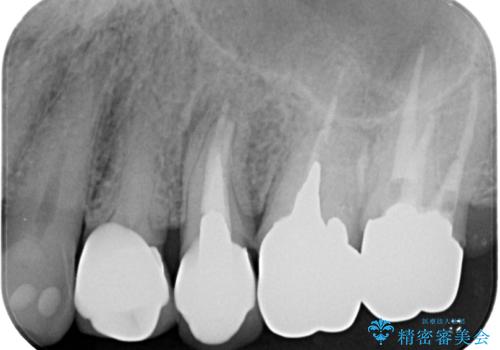

破折した奥歯 抜歯即時埋入インプラントによる補綴治療

- 舌側に膿の出口がずっと消えずに有り続けることを気にして来院された患者様です。

目視で歯根が破折していることが分かり、保存不可能と判断されたたため、抜歯即時埋入インプラントによる補綴治療を行うこととしました。